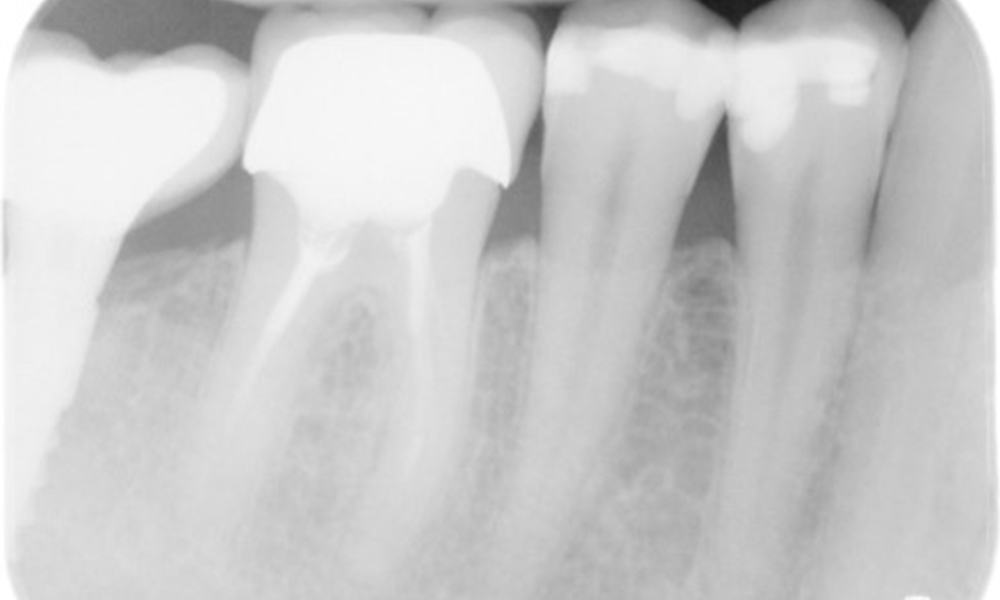

В медицинската история 55-годишният пациент заявява, че няма хронични заболявания и не приема никакви лекарства. Начинът на живот на пациента също е без забележки. Пациентът има няколко зъбни възстановявания и два импланта (2-ри и 4-ти квадрант). Въз основа на настоящите данни се установява гингивит при иначе стабилно пародонтално състояние върху редуцирания пародонт (стадий III, степен А).

Пациентът не показва особени рискови фактори със специфични дентални последици. Следователно ключовият фактор е изискването по отношение на оралното здраве. В това отношение доброто орално здраве се проявява при стабилен, редуциран пародонт. Ако при контролен преглед се установят данни за увеличаване на дълбочината при сондиране в сравнение с изходното ниво, съчетано с дифузно кървене, следва да се предприеме диагностика с помощта на рентгенова снимка (дентален рентген), за да се установи загуба на периимплантатна кост на ранен етап и да се предприемат съответните интервенции.